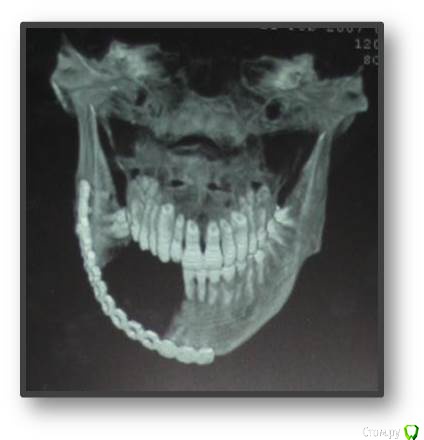

natan. Опубликовано 21 мая, 2015 Поделиться Опубликовано 21 мая, 2015 пациенту 30 лет,здоров.пришёл с букальной припулостью справа. Ссылка на комментарий

Astronaft Опубликовано 22 мая, 2015 Поделиться Опубликовано 22 мая, 2015 Очаг разрежения находится над каналом -> вероятная одонтогенная природа. Края не рваные, ровные, раздвигает зубы - гидравлический рост. 1.Одонтогенная кератокиста2. латеральная периодонтальная киста3. радикулярная киста Ссылка на комментарий

natan. Опубликовано 23 мая, 2015 Автор Поделиться Опубликовано 23 мая, 2015 Ameloblastoma mural type Ссылка на комментарий

natan. Опубликовано 24 мая, 2015 Автор Поделиться Опубликовано 24 мая, 2015 амелобластома отн-ся к группе одонтогенных опухолей.не буду останавливаться на их видах ,в данном случае диагноз unicystic ameloblastoma mural type что требует аггрессивного лечения т.е.резекция в пределах здоровых тканей.На самом деле на тему амелобластом можно говорить неограниченое время т.к. интересна своими видами и разными подходами лечения .В этом случае на 1-м этапе выполнили сегмент.резекцию и поставили reconstraction plate,на 2-м этапе free fibula (пластическими хирургами) и дальше имплантация. 3 Ссылка на комментарий